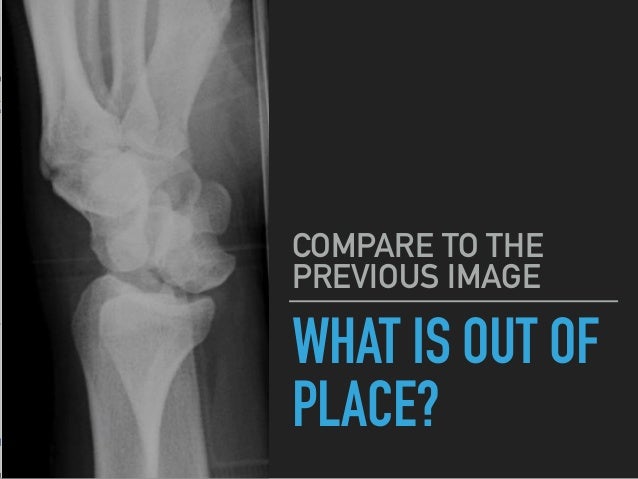

Em Rems Category Archive Wrist Xr

Hand And Wrist Radiology Key

The Wrist

Wrist Fractures Pdf